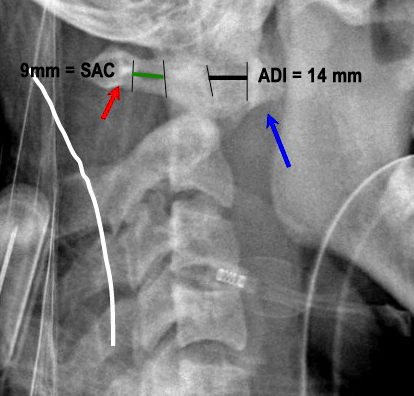

PADI>14mm

Boden and associates’ article presents compelling evidence that patients with rheumatoid arthritis and neurologic deterioration in C1-2 instability are more likely to achieve some improvement if the posterior atlanto-dens interval is greater than 10 mm on preoperative studies. All the patients in their series who had neurologic deterioration and a preoperative posterior atlanto-dens interval of greater than 14 mm achieved complete motor recovery.

Boden et al. “The most important predictor of the potential for neurological recovery after the operation was the preoperative posterior atlanto-odontoid interval (PADI). In patients who had paralysis due to atlanto-axial subluxation, no recovery occurred if the PADI was less than 10mm, whereas recovery of at least one neurological class always occurred when the PADI was at least 10mm. All patients who had paralysis and a PADI or diameter of the subaxial canal of 14mm had complete motor recovery after the operation.” They found no correlation with the anterior atlanto-odontoid interval (ADI) with the severity of paralysis or the potential for recovery.

Xrays to determine AADI and PADI:

- 3.5 mm on flex/ex

- PADI <14 mm more sensitive than AADI measurement for spinal cord compression in patients w/ RA. More sensitive for identifying patients at risk of neuro injury.

Xrays determine mechanical instability: c1-c2 relationship.

* AADI >9-10 mm= surgery due to risk of neurologic injury

* PADI <14 mm= surgery due to risk of neurologic injury

* 3.5 mm on flexion/ext views, though radiographic instability is common in RA and not necessarily indication for surgery.

PADI <14 mm more sensitive than AADI measurement for spinal cord compression in patients w/ RA. More sensitive for identifying patients at risk of neuro injury.

AAOS: patients with rheumatoid arthritis and neurologic deterioration in C1-2 instability are more likely to achieve some improvement if the posterior atlanto-dens interval is greater than 10 mm on preoperative studies. All the patients in their series who had neurologic deterioration and a preoperative posterior atlanto-dens interval of greater than 14 mm achieved complete motor recovery.